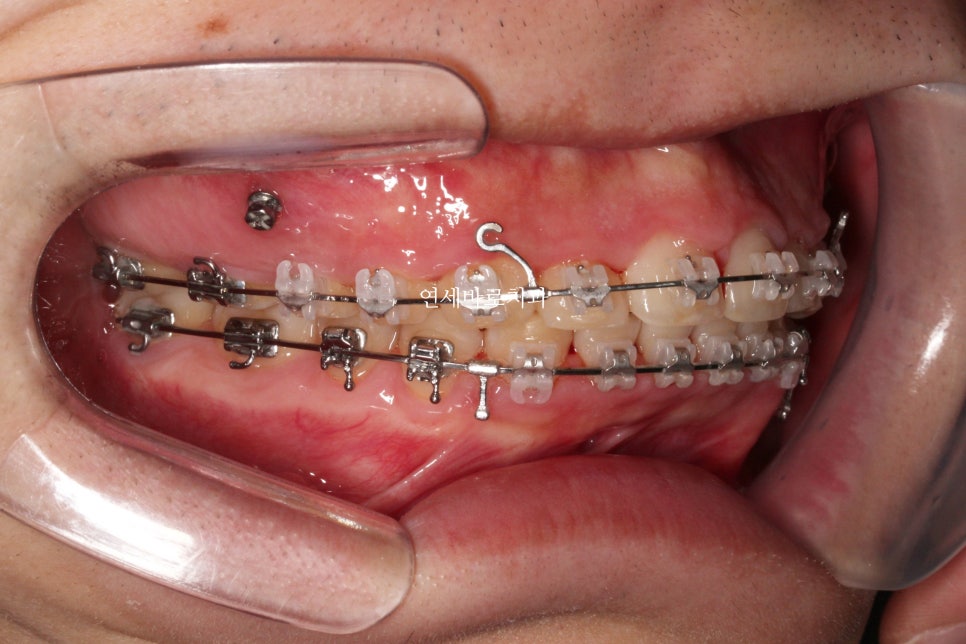

어느정도 준비를 하는 배열의 시간이 지나가고 #미니스크류 를 식립했습니다.

환자분의 골격상태 등을 고려하여 진단했고, 미니스크류를 많이 심진 않았습니다.

위쪽은 2개 심고 치료를 마무리 했습니다.

아래쪽은 중심선을 맞추기 위해 편측으로 1개만 식립.

시간이 오래 지났지만 계속 당기기만 합니다.

당기면 들어갑니다.

뒤에 공간만 있으면 뒤로 갑니다.

공간은 CT등을 통해 지속적인 확인을 하면서 진행합니다.

어금니 관계를 보면 1:1 로 만나던 치아가 사이사이 지그재그 들어가는 것이 보이죠?

약 5mm정도 후방이동 된 것으로 보입니다.

워낙 짧은 치관 길이와 골격형태가 교정치료를 하기 어려운 상황이긴 했지만,

환자분이 내원간격도 잘 지켜주시고, 오랜기간 변함없이 잘 참아주셔서 좋은 결과를 얻을 수 있었던 것으로 생각합니다.